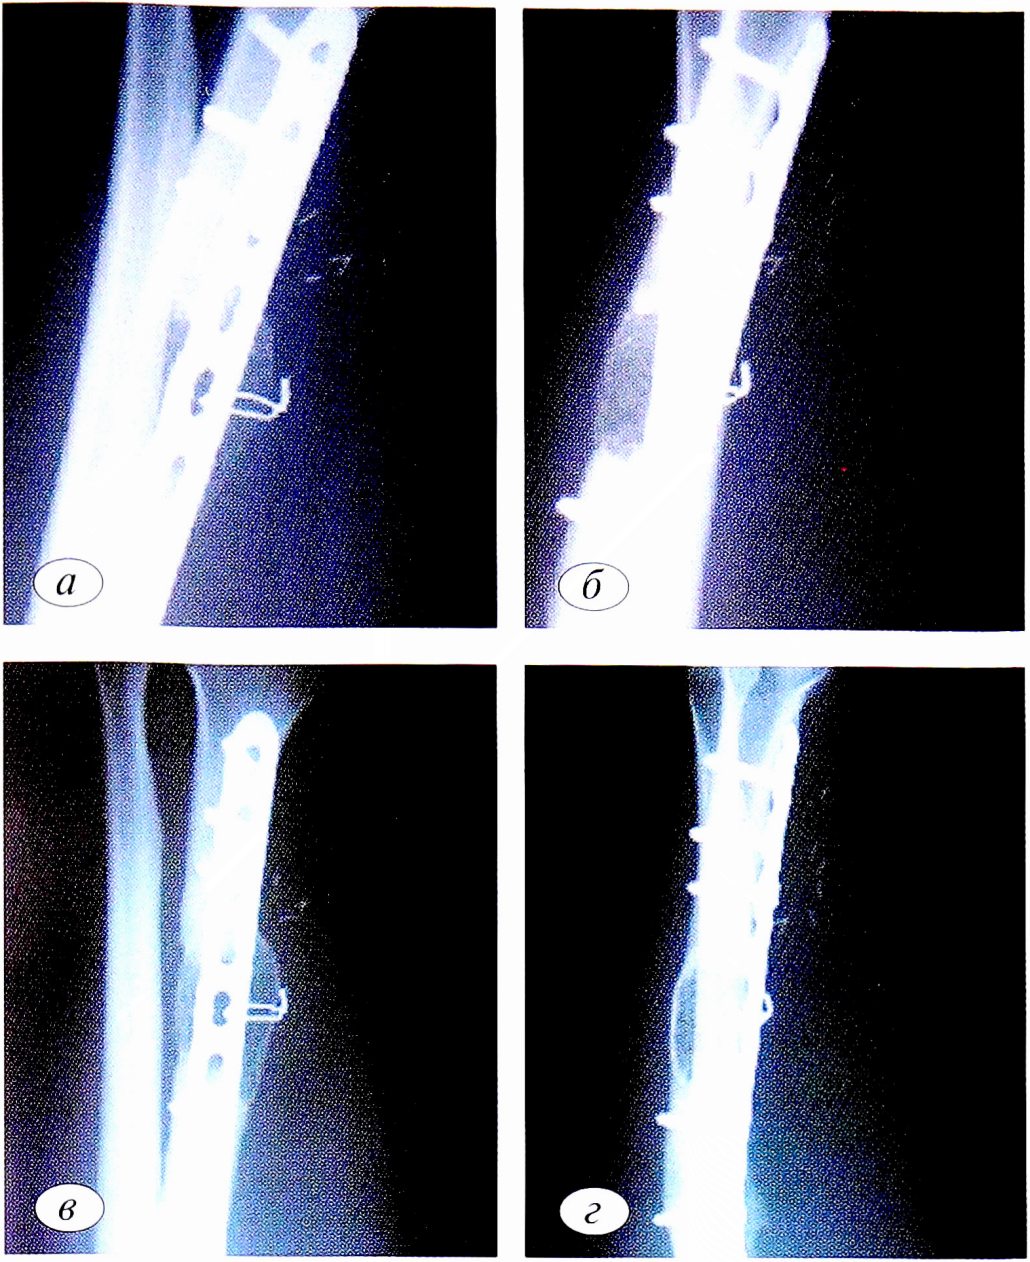

Клинический пример 2. Пациент А. в результате высокоэнергетической травмы получил открытый перелом правой лучевой кости со смещением отломков. Прооперирован в день получения травмы: выполнены остеосинтез лучевой кости аппаратом Илизарова и первичная хирургическая обработка раны. На контрольных рентгенограммах выявлены отсутствие признаков консолидации, формирование дефекта лучевой кости в связи с чем в октябре того же года прооперирован повторно: выполнены остеосинтез лучевой кости спицестержневым аппаратом, костная аутопластика из гребня подвздошной кости. При последующем наблюдении пациента в течение 2 лет обнаружены признаки формирования ложного сустава лучевой кости. Пациенту выполнена васкуляризированная костная аутопластика свободным трансплантатом из медиального мыщелка БК (рис. 3, а, б).

Рис. 3. Рентгенограммы предплечья на следующий день после операции (а, б) и через 3 мес после операции (в, г).

Fig. 3. X-rays of the forearm the day after surgery (a, b) and 3 months after surgery (c, d).

Результат, полученный через 3 мес после операции, представлен на рис. 3, в, г.